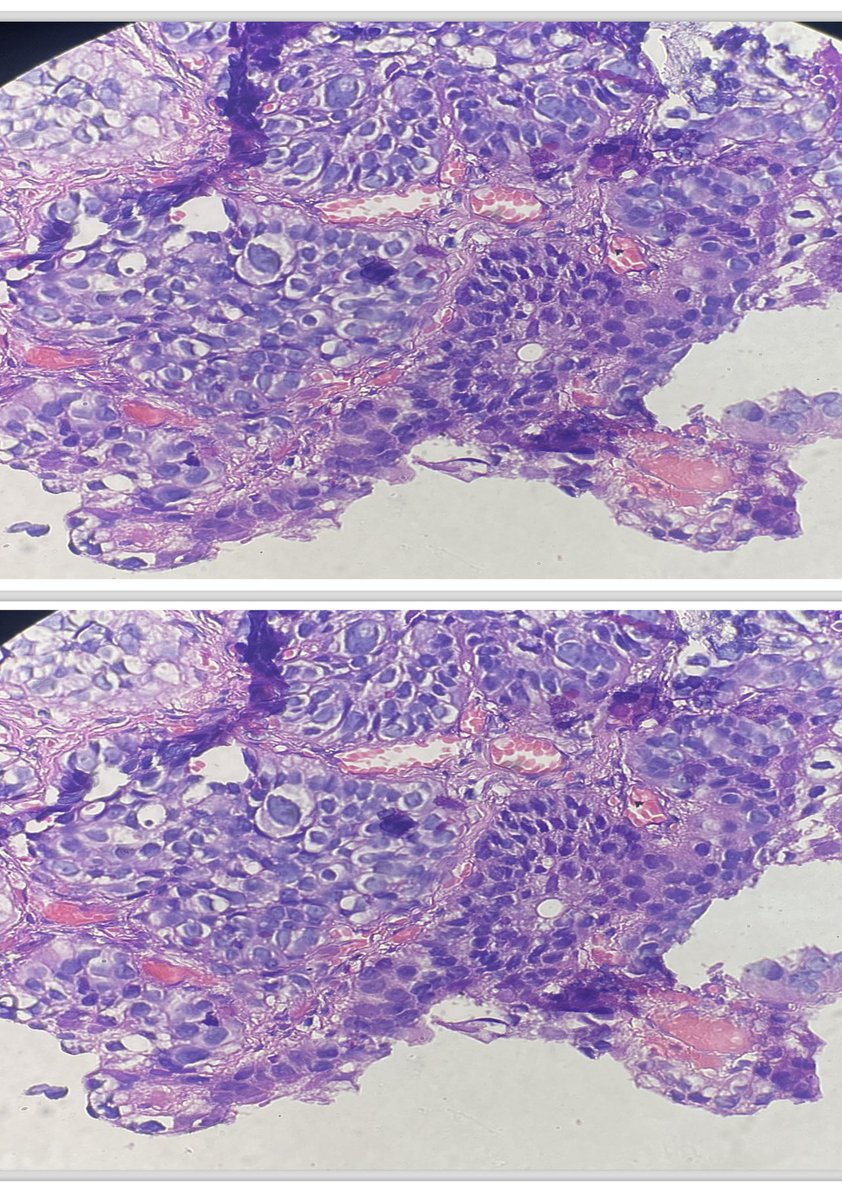

67yo male with polyploid nasal mass. A biopsy was taken. #pathology #twitterpath #headneckpath

EIacovou's tweet image. 67yo male with polyploid nasal mass.  A biopsy was taken. #pathology  #twitterpath #headneckpath